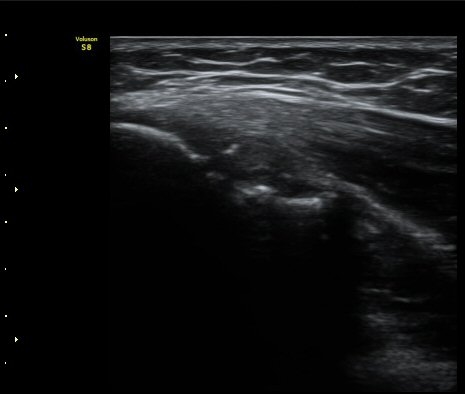

³»»ó°ú Á¾´Ü¸é°Ë»ç»ó  ³»ÃøºÎÀδë Àú¿¡ÄÚ ºÎÁ¾°ú ³»»ó°ú ÀÎ´ë ºÎÂøºÎ ÇÇÁú°ñÀÇ ºÒ±ÔÄ¢º¯È­¿Í

°ñÆíÀÌ °üÂûµÇ°í(±×¸² 1, 2, 3, 4) ÀÌ·±¼Ò°ßÀº °ÇÃø°ú ºñ±³ÇÏ¸é ´õ¿í ¶Ñ·ÈÇÔ(±×¸² 5, 6).